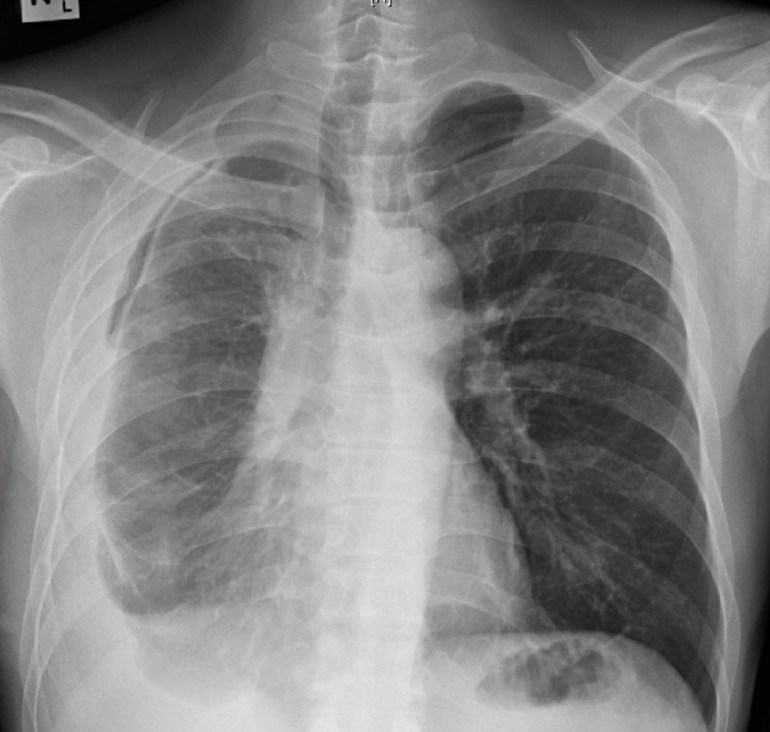

A middle-aged man who had renal transplantation 5 years ago (but otherwise well) presented with fever and shortness of breath for 2 weeks. He was found to have a right pleural effusion on chest X-ray, and underwent a diagnostic pleural tap. The TB PCR was positive from the pleural fluid, and he was started on standard anti-tuberculosis therapy (but with levofloxacin substituted for rifampicin owing to the interactions of the latter drug with other agents taken to maintain the renal transplant). The initial chest X-ray and the subsequent chest X-ray taken 10 days later are shown below.

Initial chest X-ray of the man with renal transplant, showing a right-sided loculated pleural effusion.